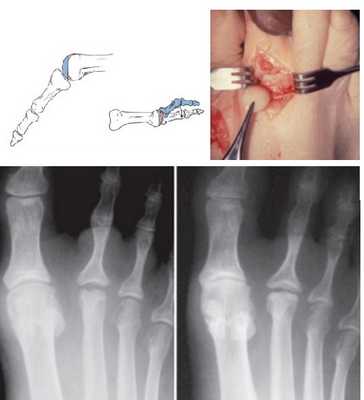

Классификация аваскулярного некроза головок плюсневых костей.

Субхондральный перелом, виден только на МРТ

Коллапс тыльной суставной поверхности

Коллапс всей тыльной части головки, подошвенная часть интактна

Коллапс всей головки, сужение суставной щели

Прогрессирование деформирующего артроза, облитерация суставной щели

На ранних стадиях используется гипсовая иммобилизация в короткой циркулярной гипсовой повязке стопа-голеностоп на срок 4-6 недель. После окончания иммобилизации используется ортопедическая обувь с жёсткой подошвой и подкладками в области головки второй плюсневой кости.

В случае отсутствия эффекта от консервативного лечения показано опреативное вмешательство.

Используется 3 основных вида оперативных вмешательств: артротомия и дебридмент, дорсальная клиновидная остеотомия, частичная резекция головки плюсневой кости.

Артротомия и дебридмент в настоящее время применяется всё реже. Помимо удаления свободных хондромных тел, резекции воспаленной синовиальной оболочки, могут применяться рассверливание головки плюсневой кости, интерпозиция сухожилия длинного разгибателя пальцев в полость сустава.

В первых трёх стадиях заболевания хорошо себя зарекомендовала тыльная клиновидная остеотомия, которая позволяет одновременно удалить очаг деструкции и поставить на его место сохранившуюся и кровоснабжаемую подошвенную часть головки плюсневой кости.

Частичная резекция головки плюсневой кости, или операция DuVries, показана при 4,5 стадиях заболевания, когда подошвенная часть не позволяет выполнить клиновидную остеотомию. Может быть дополнена интерпозицией суставной капсулы в полость сустава.